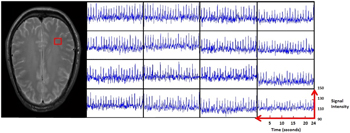

We used the echo planar imaging (EPI) time series (as described in section 3) in human volunteers at rest. The beginning of the sequential RF-pulses train of the EPI time series were used to saturate the magnetization of the imaging slice. The desired reductions of the local NMR component were normally reached shortly before the equilibrium magnetization. Then, we found regular, repeating signal bursts of predominant signal alternations in single volumes of the brain slices as shown in figure 1, where the signal peaks of the bursts increased by up to 15%. In most cases, the alteration was sequential from one image acquisition to the next.

Figure 1. MRI signal time course (Black) during 12 heart cycles compared with simultaneous oximeter reading of a finger (Grey).

Standard image High-resolution imageFigure A3. 4 × 4 voxel matrix randomly picked. On the left, the red square shows location in the brain slice. On the right, 16 corresponding signal time courses displaying the local tissue responses over a time period of 24s.